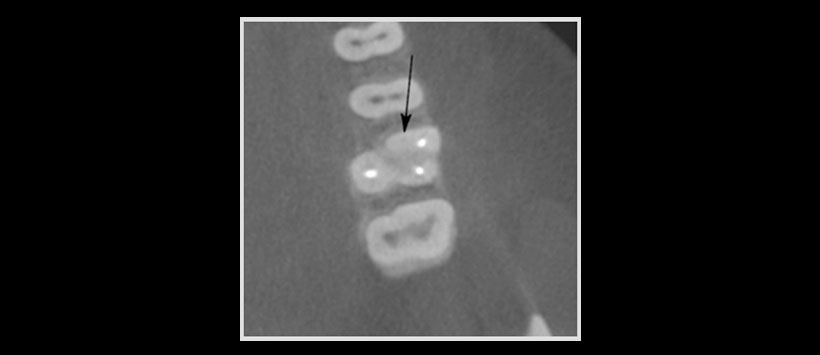

Figura 1: Una exploración axial CBCT de un molar superior con un segundo canal mesiovestibular no obturado.